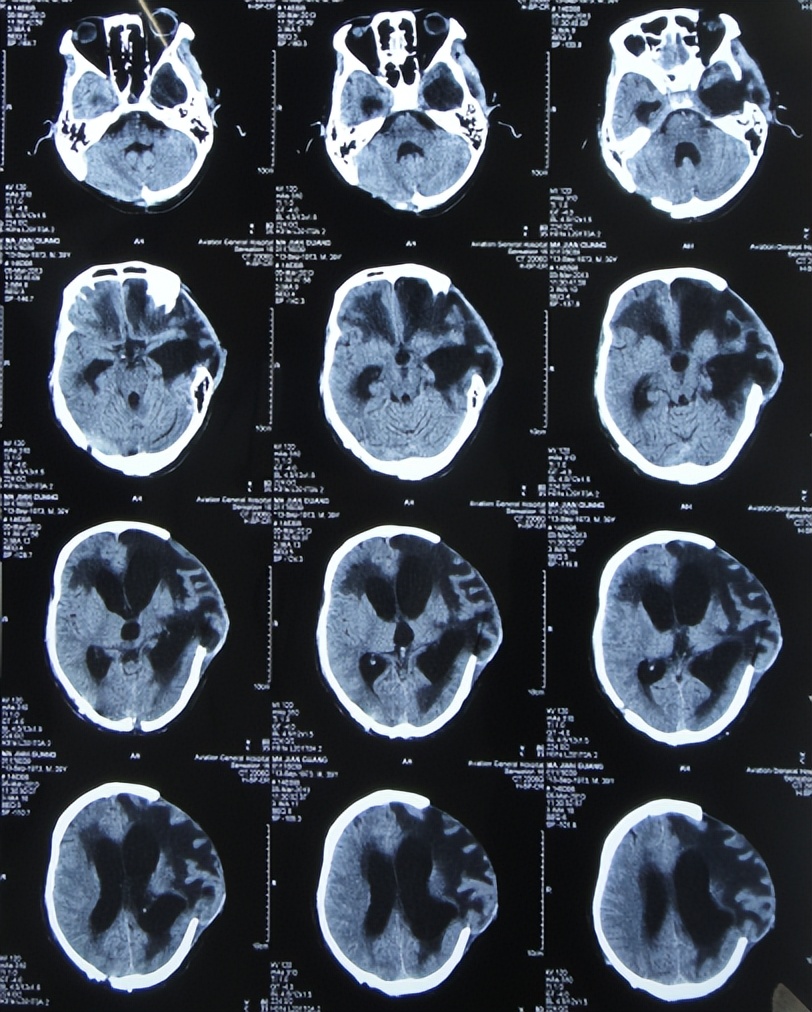

患者于2012年12月7日,骑电动车意外摔伤致脑外伤昏迷,急送往当地的河北省邯郸市的某三甲医院,查头颅CT示脑挫裂伤,有出血( 图-1 ),急诊给予了左额颞顶及右枕开颅颅内血肿清除并去骨瓣减压术,留置脑室外引流。患者既往病史:19岁时曾患肺结核已治好。

图-1: 2012年12月7日头颅CT

术后次日查头颅CT示开颅去骨瓣减压术后状态,有水肿( 图-2 )。

图-2: 2012年12月8日头颅CT

开颅术后5天即2012年12月12日,查头颅CT示仍有水肿,但拔除了脑室外引流管( 图-3 )。

图-3: 2012年12月12日头颅CT

开颅术后7天即2012年12月14日,查头颅CT示水肿有加重( 图-4 )。

图-4: 2012年12月14日头颅CT